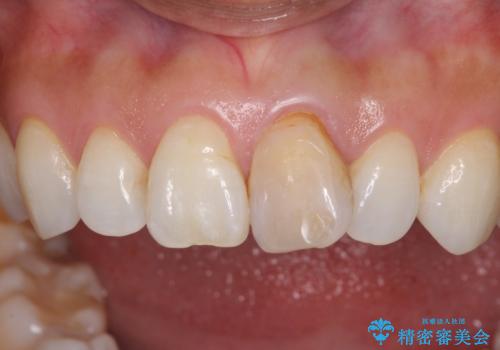

- 10年以上前に神経を取り除いた前歯の変色が気になるとのことで来院された患者様です。

レントゲン写真より、歯根の炎症が認められなかったため、ファイバーコアによる土台築製後、オールセラミッククラウンにて補綴することとしました。